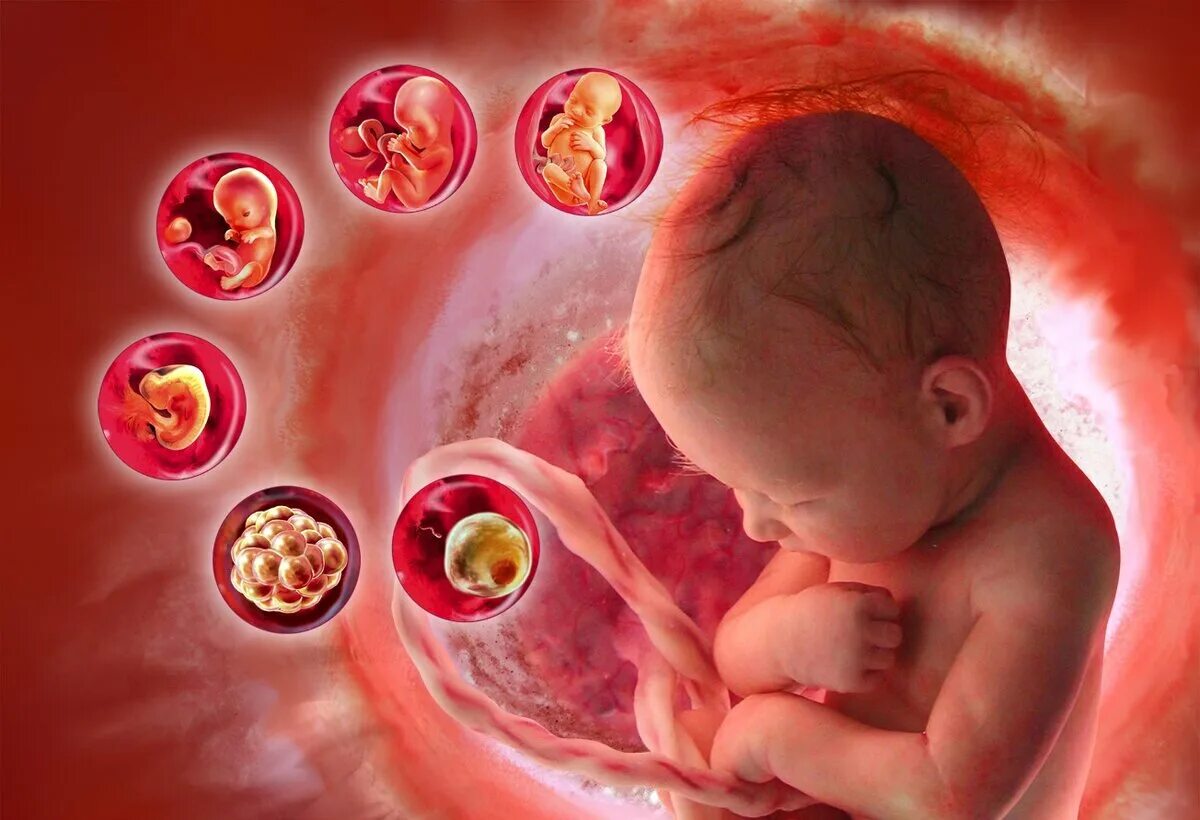

Куда девается эмбрион